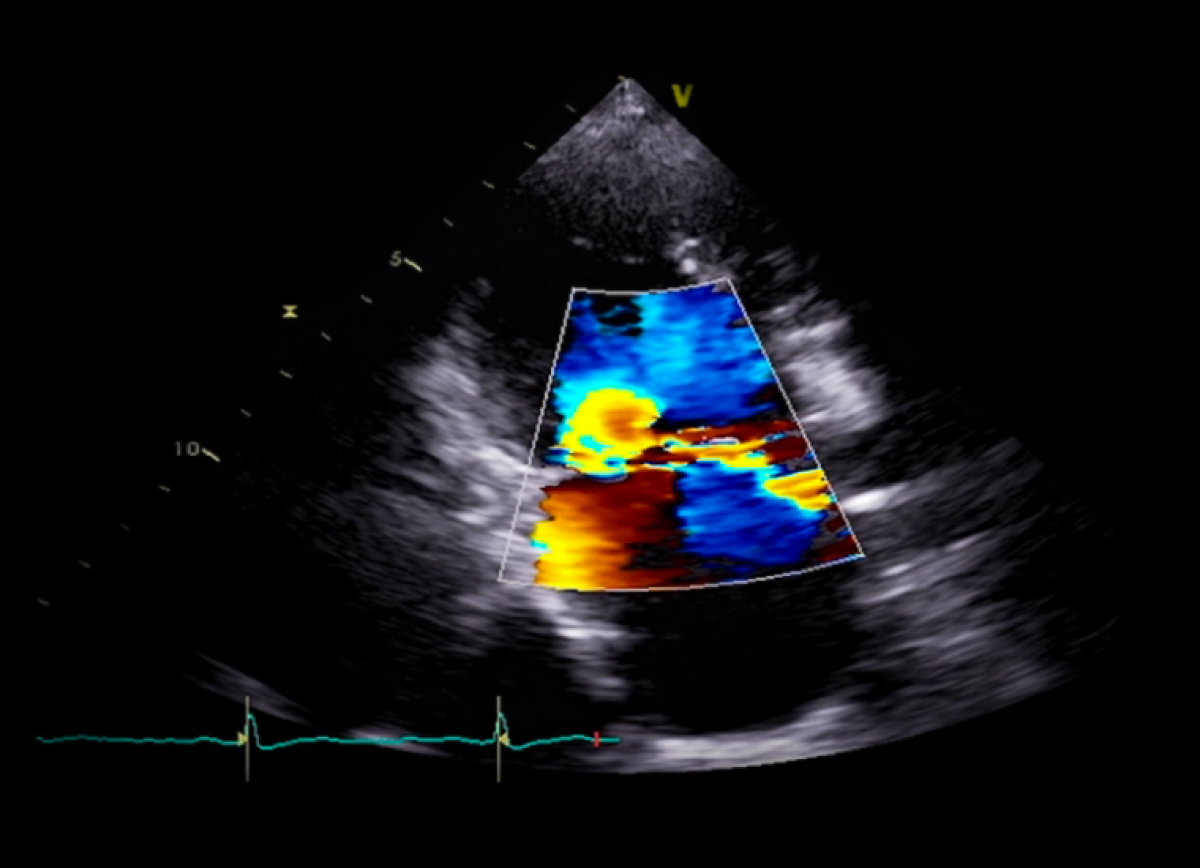

Pacjent z pogorszeniem tolerancji wysiłku, kołataniami serca i głośnym szmerem holosystolicznym

Ciężka niedomykalność mitralna na tle wypadania płatka z zerwaniem struny ścięgnistej

Ocena pierwotnej niedomykalności mitralnej